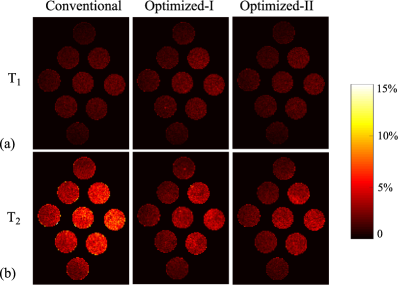

III-B Phantom Experiments

We evaluated the proposed approach with phantom experiments. Here we focus on the scenario of highly-undersampled MR fingerprinting experiments, which is of the most practical interest for quantitative MR imaging. Specifically, we created a physical phantom that consists of 9 plastic tubes, each one filled with a solution of Gadolinium and Agar at different concentrations. This created different combinations of T1subscript𝑇1T_{1} and T2subscript𝑇2T_{2} values that are relevant to the neuroimaging application [52]. We carried out the experiments on a 3T Siemens Tim Trio scanner (Siemens Medical Solutions, Erlangen, Germany) equipped with a 32-channel head array coil. The relevant imaging parameters include: FOV = 300×300mm2300300superscriptmm2300\times 300~{}\mathrm{mm}^{2}, matrix size = 256×256256256256\times 256, and slice thickness = 5mm5mm5~{}\mathrm{mm}.

III-B1 General evaluation

We performed three sets of experiments with N=400𝑁400N=400, respectively, using the acquisition parameters from the conventional scheme, Optimized-I, and Optimized-II. We used the same spiral trajectory and sampling pattern as in the numerical simulations. Here the acquisition times for the conventional scheme, Optimized-I, and Optimized-II were 5.28 sec, 5.24 sec, and 5.22 sec, respectively. To evaluate the performance of the above experiments, we also acquired a set of reference T1subscript𝑇1T_{1} and T2subscript𝑇2T_{2} maps, by performing a fully-sampled MR fingerprinting experiment777The fully-sampled experiment was performed by repeating a highly-undersampled acquisition 48 times. For each acquisition, we switched to a different spiral interleaf at every time point. Note that a short time delay was added between consecutive acquisitions to ensure that the magnetization starts at thermal equilibrium. with N=1000𝑁1000N=1000 using the acquisition parameters from the conventional scheme. The acquisition time for this experiment was about 18 min. Additionally, we calibrated the spiral trajectory with a specialized pulse sequence [53] to avoid the potential trajectory distortion (caused by eddy currents and gradient delay). Finally, we performed an auxiliary scan with a gradient echo (GRE) sequence, from which we estimated the coil sensitivity maps. This acquisition took 1.28 sec.

We performed the ML reconstruction for the above experiments, and incorporated the slice-profile correction [54] into the dictionary. Fig. 13 shows the reconstructed T1subscript𝑇1T_{1} and T2subscript𝑇2T_{2} maps, the relative error maps (evaluated with respect to the reference data), and the corresponding reconstruction errors over each tube. It is clear that Optimized-II significantly improves the accuracy of the T2subscript𝑇2T_{2} map over the conventional scheme, while providing similar accuracy for the T1subscript𝑇1T_{1} map. Compared to Optimized-I, Optimized-II also provides better accuracy, particularly for T1subscript𝑇1T_{1} maps. This confirms the benefits of introducing the constraint on the flip angle variation for highly-undersampled MR fingerprinting experiments.

III-B2 Evaluation of cross-scan variance

Refer to caption

Figure 14: Normalized standard deviation maps associated with the conventional acquisition, Optimized-I, and Optimized-II, estimated from 15 independent imaging experiments. (a) Normalized standard deviation maps for T1subscript𝑇1T_{1}. (b) Normalized standard deviation maps for T2subscript𝑇2T_{2}.

Figure 15: Normalized standard deviation averaged over each tube for (a) T1subscript𝑇1T_{1} and (b) T2subscript𝑇2T_{2}.

Given that variance reduction is a direct benefit of the CRB based experiment design [33], we evaluated the variance associated with the three acquisition schemes. Specifically, we conducted each acquisition 15 times, and calculated the normalized standard deviation associated with each acquisition scheme. With the absence of the ground truth for the phantom experiments, the standard deviations were normalized with respect to the parameter maps reconstructed from the fully-sampled data with N=1000𝑁1000N=1000. Fig. 14 shows the normalized standard deviation maps for the three acquisition schemes, and Fig. 15 shows the normalized standard deviation averaged over each tube. It is evident that the two optimized experiments substantially reduce the standard deviation for T2subscript𝑇2T_{2} maps, while providing similar standard deviation for T1subscript𝑇1T_{1} maps. In particular, Optimized-II achieves a factor of two reduction in the standard deviation of T2subscript𝑇2T_{2} maps for all the tubes.